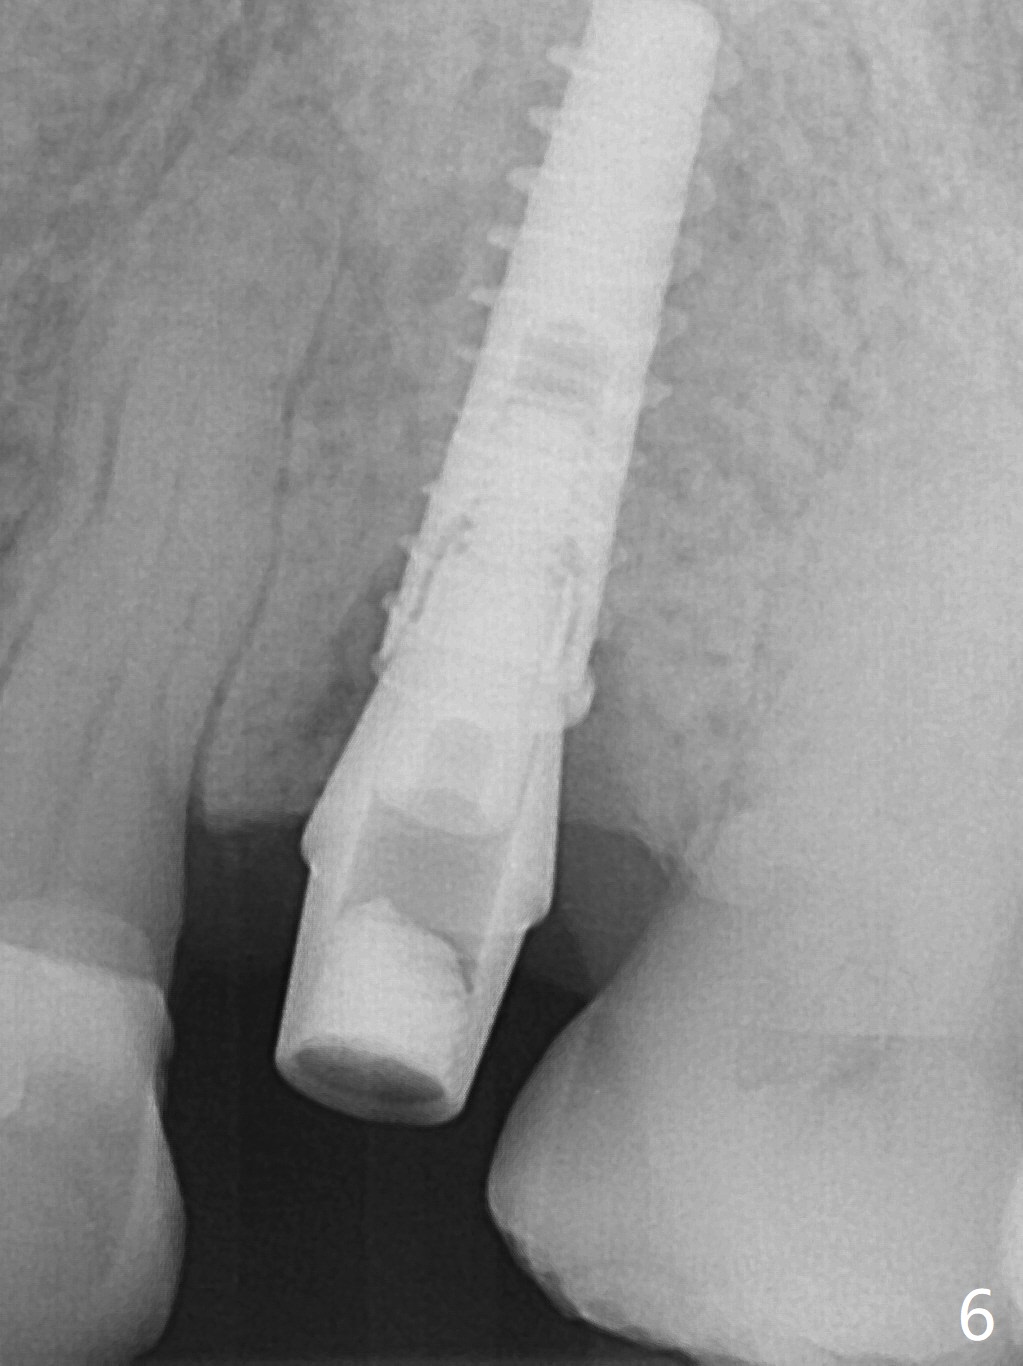

A 74-year-old man has diabetes. Implant osteointegration appears to be slow at #4, while the implant at #28 failed once. He requests implant at #13 (Fig.1). It seems that the bone is wide enough (8 mm, Fig.2 (CT coronal section) (P: palatal)) to hold a 4 mm implant (Fig.3 (axial section)). Since bone density is low at the coronal (100-200 units) and middle (50-100 units) segments (Fig.2), bone condensation will be beneficial. To facilitate wound healing, flapless approach is adopted using 1.6 mm pilot drill (Fig.4), followed by 1.4/2.6 mm bone expander. In fact there is resistance to expansion in the zone 1. Magic expander (3.0 mm) is also tried with difficulty. It appears that bone density is higher than expected. The second portion of Magic Surgical Kit is then used: 3.3 mm Magic Drill for 15 mm (gingival level, followed by Final Drill). A 4x13 mm IBS implant is seated incompletely. The osteotomy is further enlarged by 3.8 mm Magic Drill for 11 mm and deepened with 3 mm drill until 18 mm. Finally the implant is placed at a satisfactory level with insertion torque > 50 Ncm (Fig.5). A 4.5x4(3) mm abutment is placed and periodontal dressing is applied. The patient chooses to return for impression 6 months postop (Fig.6). The abutment changes to a 4x4(4) mm one. The crown is recemented nearly 2 years post cementation, which is related to distal and deep placement of the implant and bruxism (Fig.7).